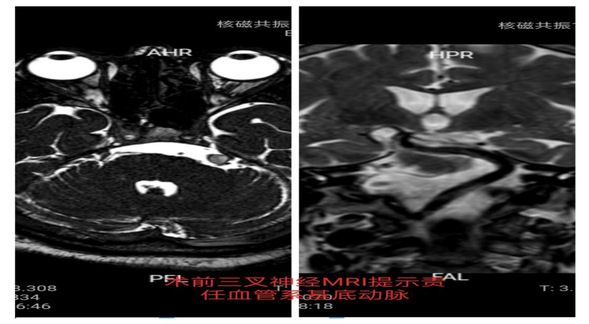

王云龙副主任医师根据患者的病情及身体状况为该患者制定了个体化的治疗方案,因患者年龄较高,经严格的药物治疗效果不佳,恐惧开颅手术对微血管减压术依从性较差,术前三叉神经MRI检查提示患者系较粗大的椎基底动脉移位压迫左侧三叉神经根,患者长期高血压脑动脉硬化,经颅行微血管减压将血管推离三叉神经根且悬吊难度大,老人家不愿意行选择性三叉神经感觉根切断术,综合以上因素为老人家制定经皮穿刺三叉神经半月结微球囊压迫术的手术方案。该术式属于神经外科介入手术,在C型臂或脑血管造影机或神经外科手术机器人的定位下进行,手术时间短,且具有微创、无血、恢复快的优点,面部仅仅一个针孔,术后无任何痕迹,且费用低。老人家欣然接受,手术如期进行,麻醉诱导完成后,手术用时15分钟,术后疗效立竿见影,疼痛完全消失,折磨患者5年的三叉神经痛终于获得成功治愈,老人家脸上终于露出了久违的笑容,患者于术后第二日即康复出院。

术前三叉神经MRI提示基底动脉移位压迫左侧三叉神经根部